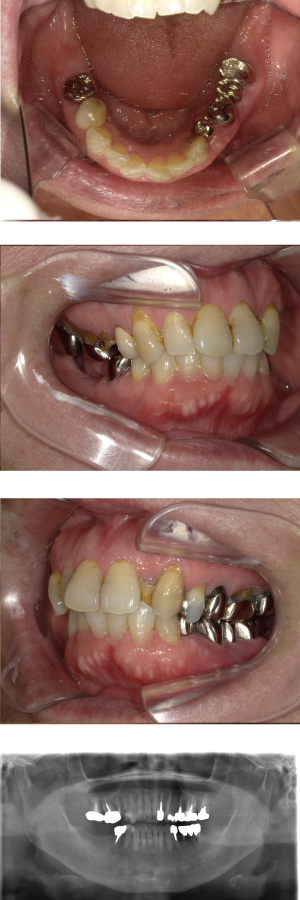

50代 女性 インプラント治療(GBR・ソケットリフト)

| 年代・性別 | 50代・女性 |

|---|---|

| 主訴 | Brの歯が取れそうなため、インプラントに変えたい。 |

| 部位 | 左下567 左上④5⑥ 右上67 |

| 治療期間 | 約3年9ヶ月 |

| 費用 | ¥3,224,500(税込) |

| 副作用・リスク |

|